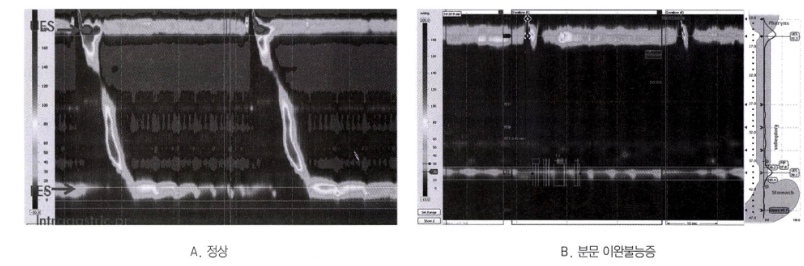

이완불능증 (Achalasia)

• 정의: 하부식도괄약근(LES)이 이완되지 않고 식도 체부의 연동운동이 소실되는 질환

• 원인: 식도 근육층 신경총(Auerbach's plexus)의 신경절 세포 소실이 원인으로 추정됨. Chagas 병에서도 유사한 소견이 나타날 수 있음.

• 진단

• 바륨 식도조영술: 식도 체부의 확장과 하부의 '새 부리 모양(bird's beak)' 협착 소견

• 식도내시경: 확장된 식도, 송기 시 하부 식도 괄약근이 열리지 않음 (hypertrophic LES)

• 식도내압검사: 진단에 가장 중요한 검사. LES 이완 부전, 식도 연동운동 소실 확인